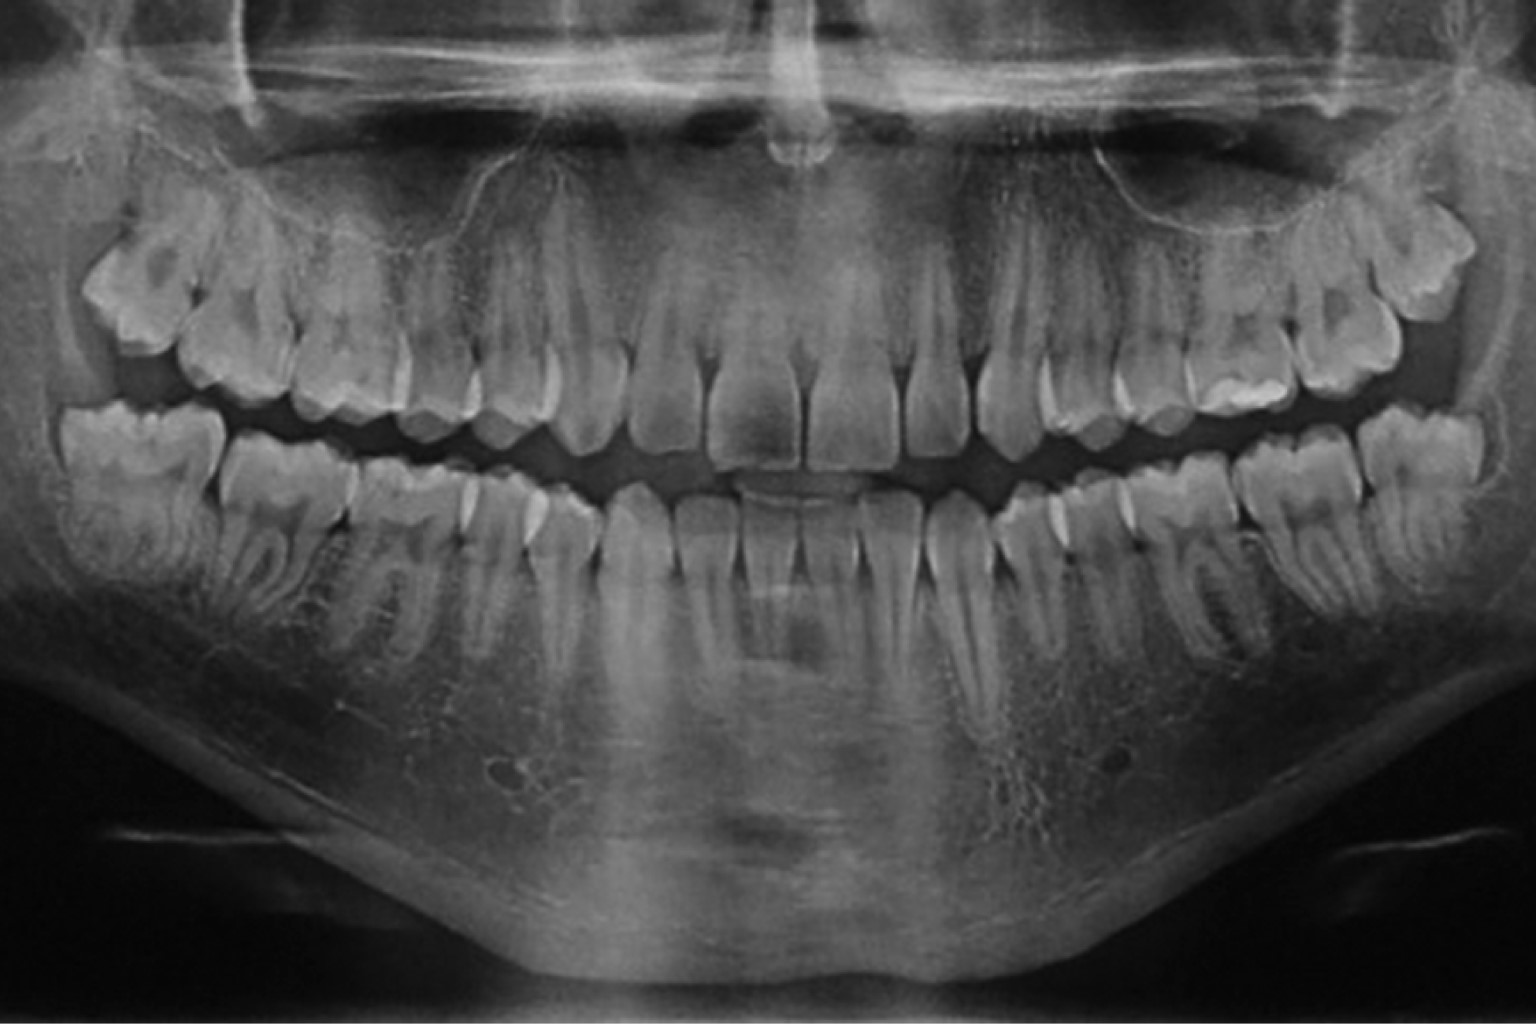

Caso 2. Hombre de 22 años de edad, quien acude a la Clínica Universitaria de Atención a la Salud (CUAS) Estado de México de la Facultad de Estudios Superiores Zaragoza (FES-Z) de la Universidad Nacional Autónoma de México (UNAM) por presentar episodios repetitivos de pericoronitis asociada al tercer molar inferior derecho parcialmente erupcionado. Al interrogatorio sin antecedentes médicos y dentales de importancia. Al realizar la exploración física intrabucal se observó que dicho órgano dentario presentaba macrodoncia y morfología irregular, por lo que se sospechó de fusión con un distomolar (Figura 3), lo cual se corroboró con la evaluación radiográfica (Figura 4) y del espécimen quirúrgico postodontectomía (Figura 5). El cuarto molar se encontraba fusionado en el aspecto distal del tercer molar y la unión se presentaba a nivel coronal y radicular compartiendo la misma cámara pulpar (Figura 6).